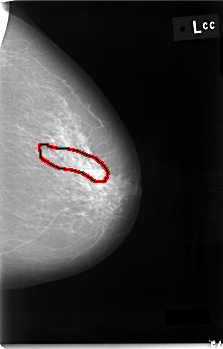

C_0002_1.LEFT_CC

LEFT_CC LINES 5928 PIXELS_PER_LINE 3776 BITS_PER_PIXEL 12 RESOLUTION 50 OVERLAY

FILE: C_0002_1.LEFT_CC.OVERLAY

TOTAL_ABNORMALITIES 1

ABNORMALITY 1

LESION_TYPE CALCIFICATION TYPE PLEOMORPHIC DISTRIBUTION SEGMENTAL

ASSESSMENT 4

SUBTLETY 2

PATHOLOGY MALIGNANT

TOTAL_OUTLINES 1

BOUNDARY